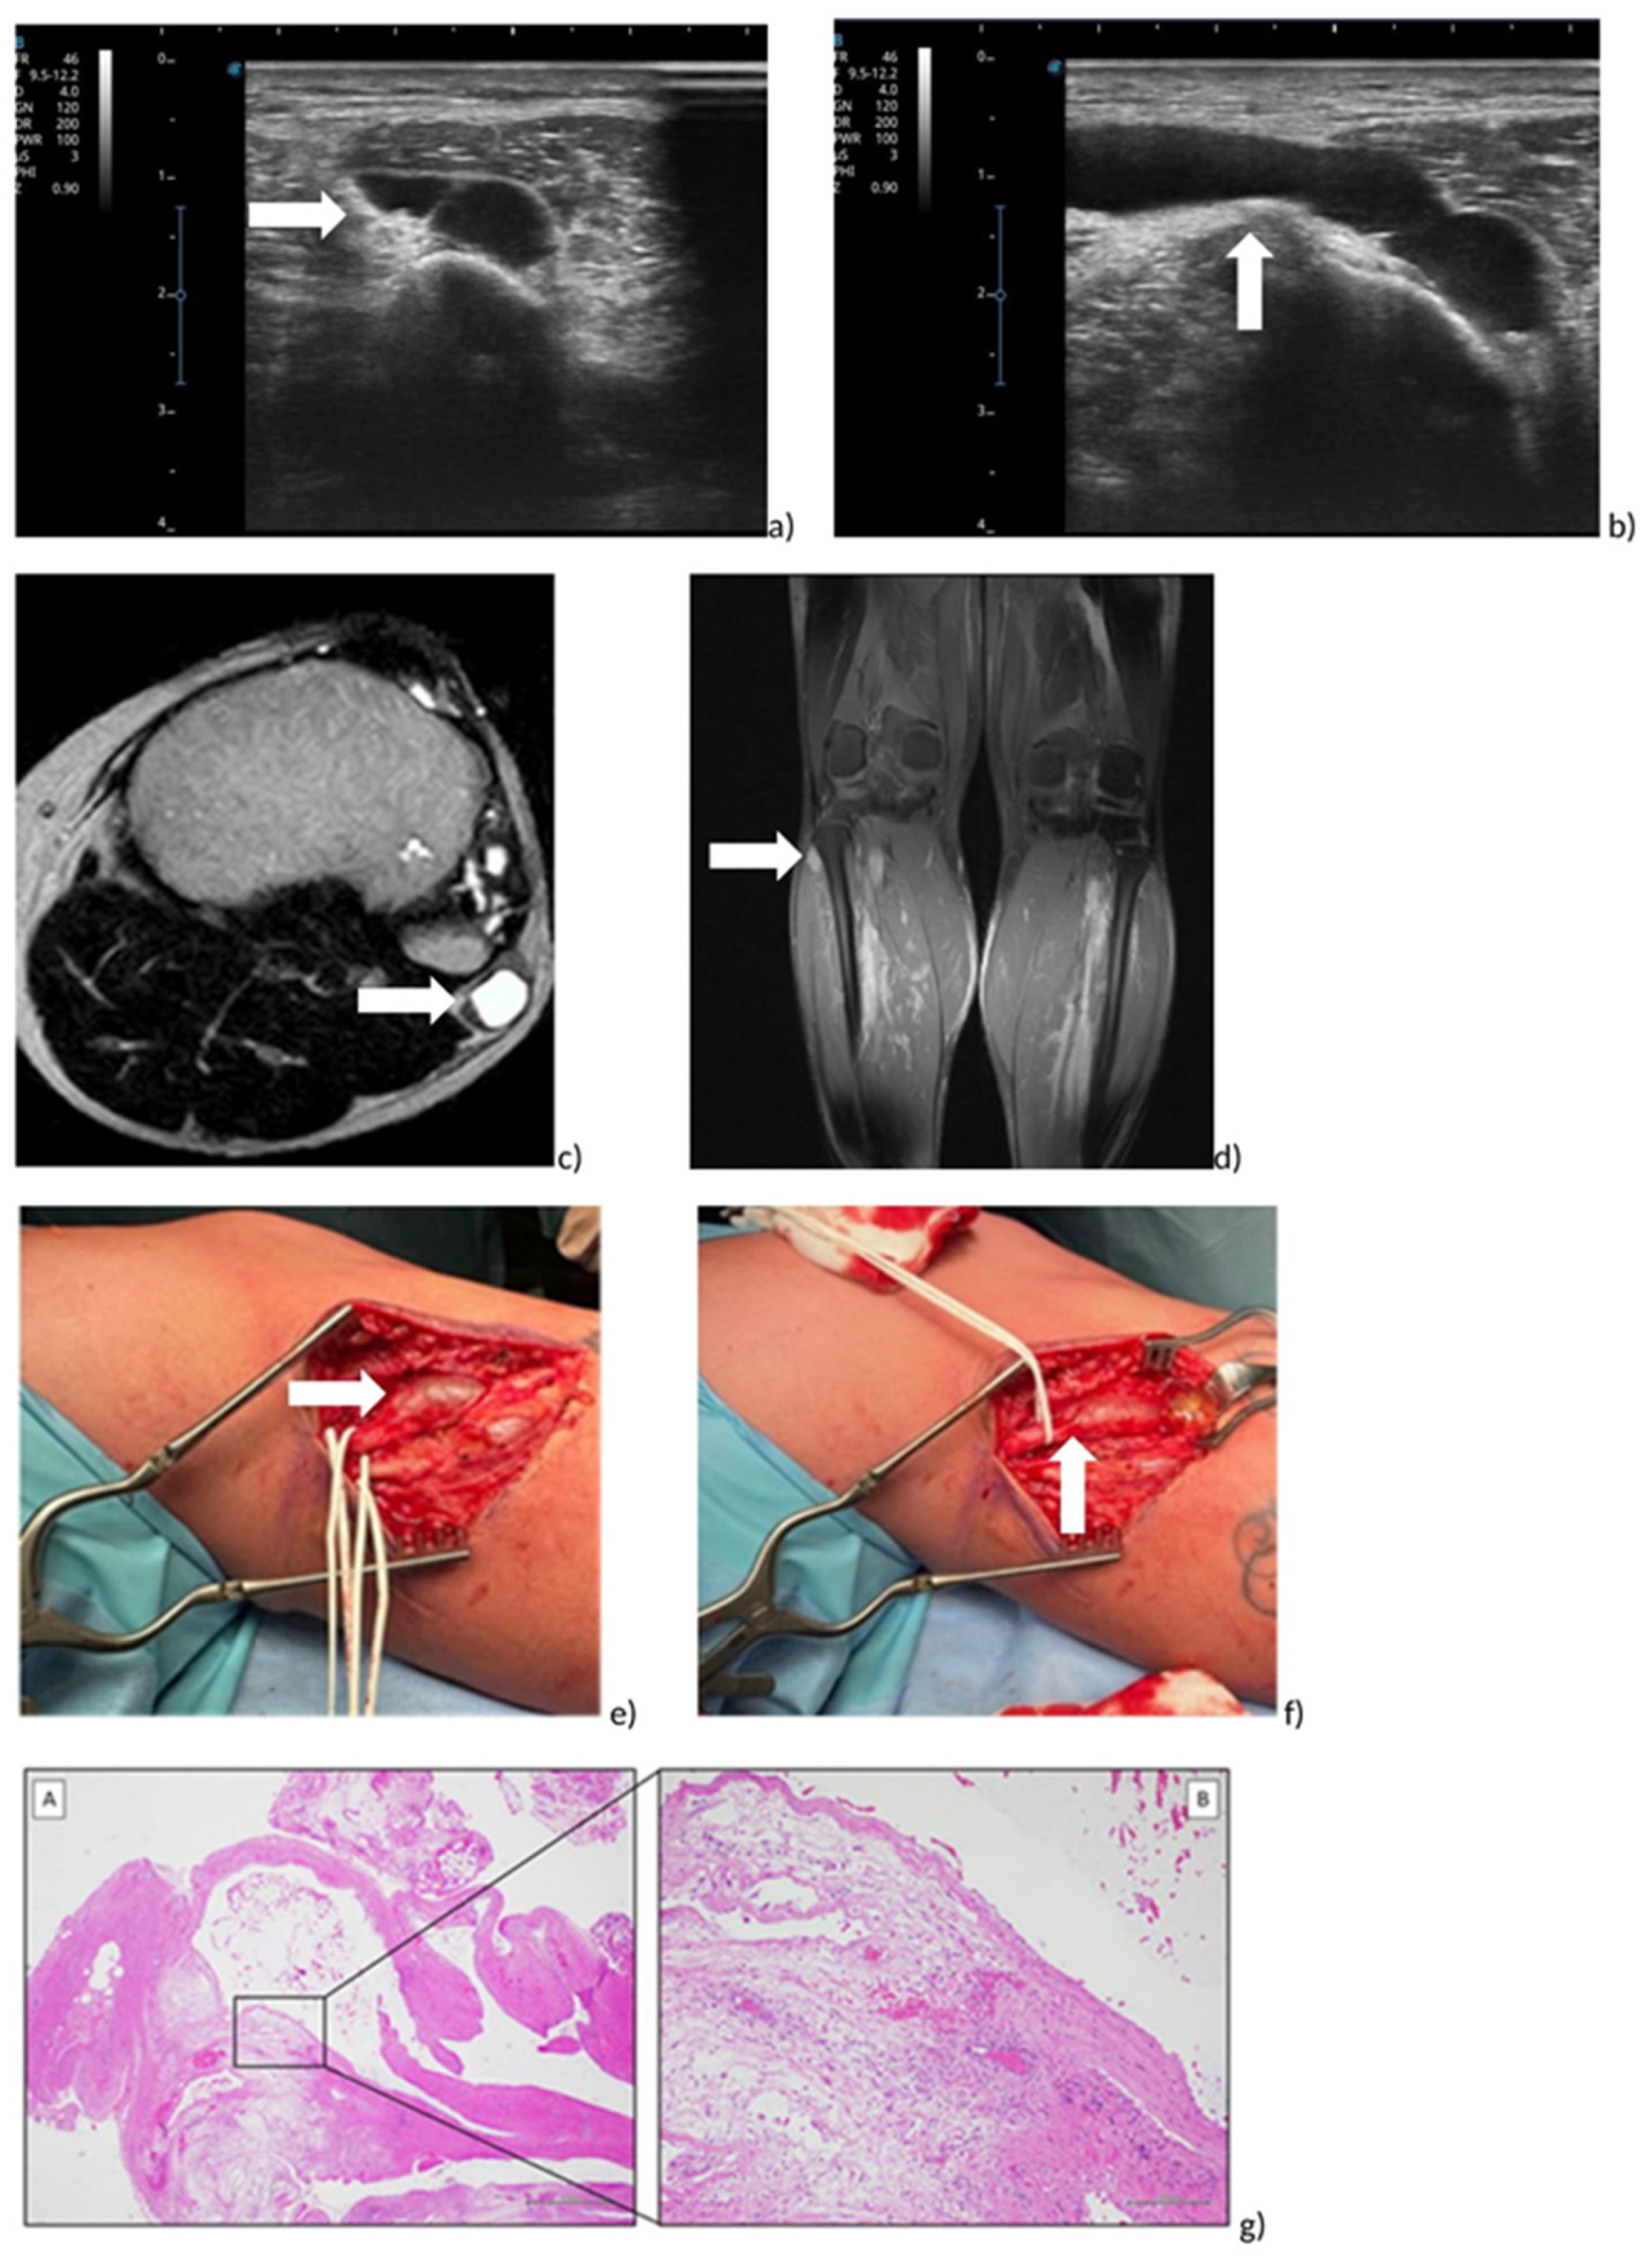

3.2. Case Report

3.2.1. Evaluation

3.2.2. Treatment

3.2.3. Follow-Up